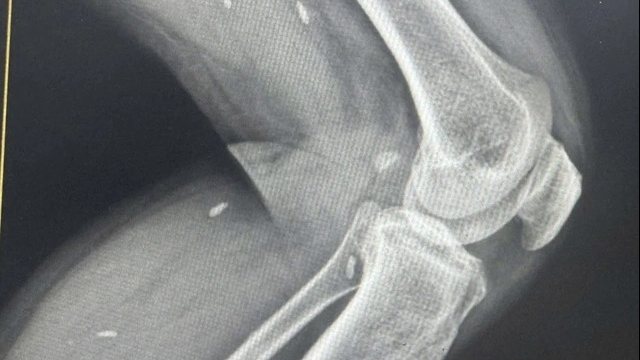

| Công ty Cổ phần Bibomart TM (120 Trần Duy Hưng, phường Trung Hòa, quận Cầu Giấy, Hà Nội bị Thanh tra Sở y tế Hà Nội xử phạt đợt này |

Công ty Cổ phần Bibomart TM (120 Trần Duy Hưng, phường Trung Hòa, quận Cầu Giấy, Hà Nội) bị xử phạt 17,5 triệu đồng do hàng hóa có nhãn phụ ghi không đúng các nội dung bắt buộc trên nhãn hàng hóa theo quy định của pháp luật về nhãn hàng hóa (tổng giá trị hàng hóa vi phạm là 52.756.848 đồng).